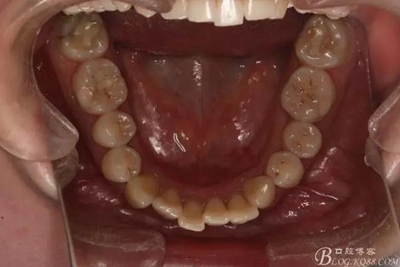

如圖,該病例為簡單排齊病例,但77鎖合是矯治中的關(guān)鍵所在,你會怎么處理?

該病例主要為17、27頰側(cè)位同時伴有伸長,當(dāng)然種植支抗可以解決,但還有簡單實用的辦法嗎?如圖,在橫腭桿遠中延伸出牽引鉤,位置盡量遠離合平面,7粘舌側(cè)扣,牽引力的方向為壓低及舌向,下圖為兩個月的效果,17已到位,27還未到位。